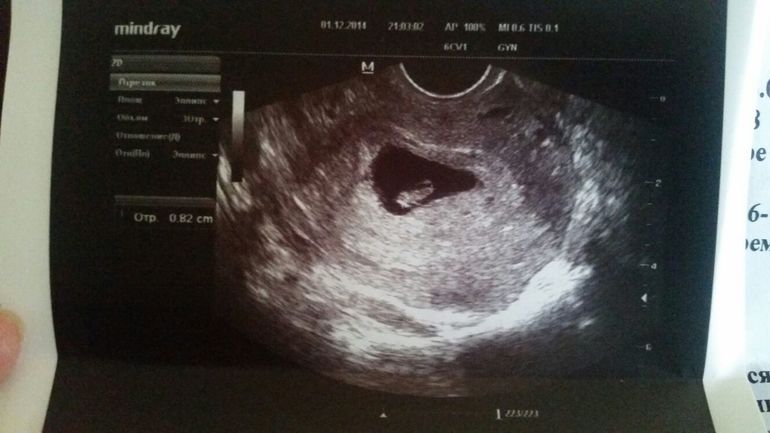

Узи 6 недель нет сердцебиения

Узи 6 недель нет сердцебиения 119 фотографий